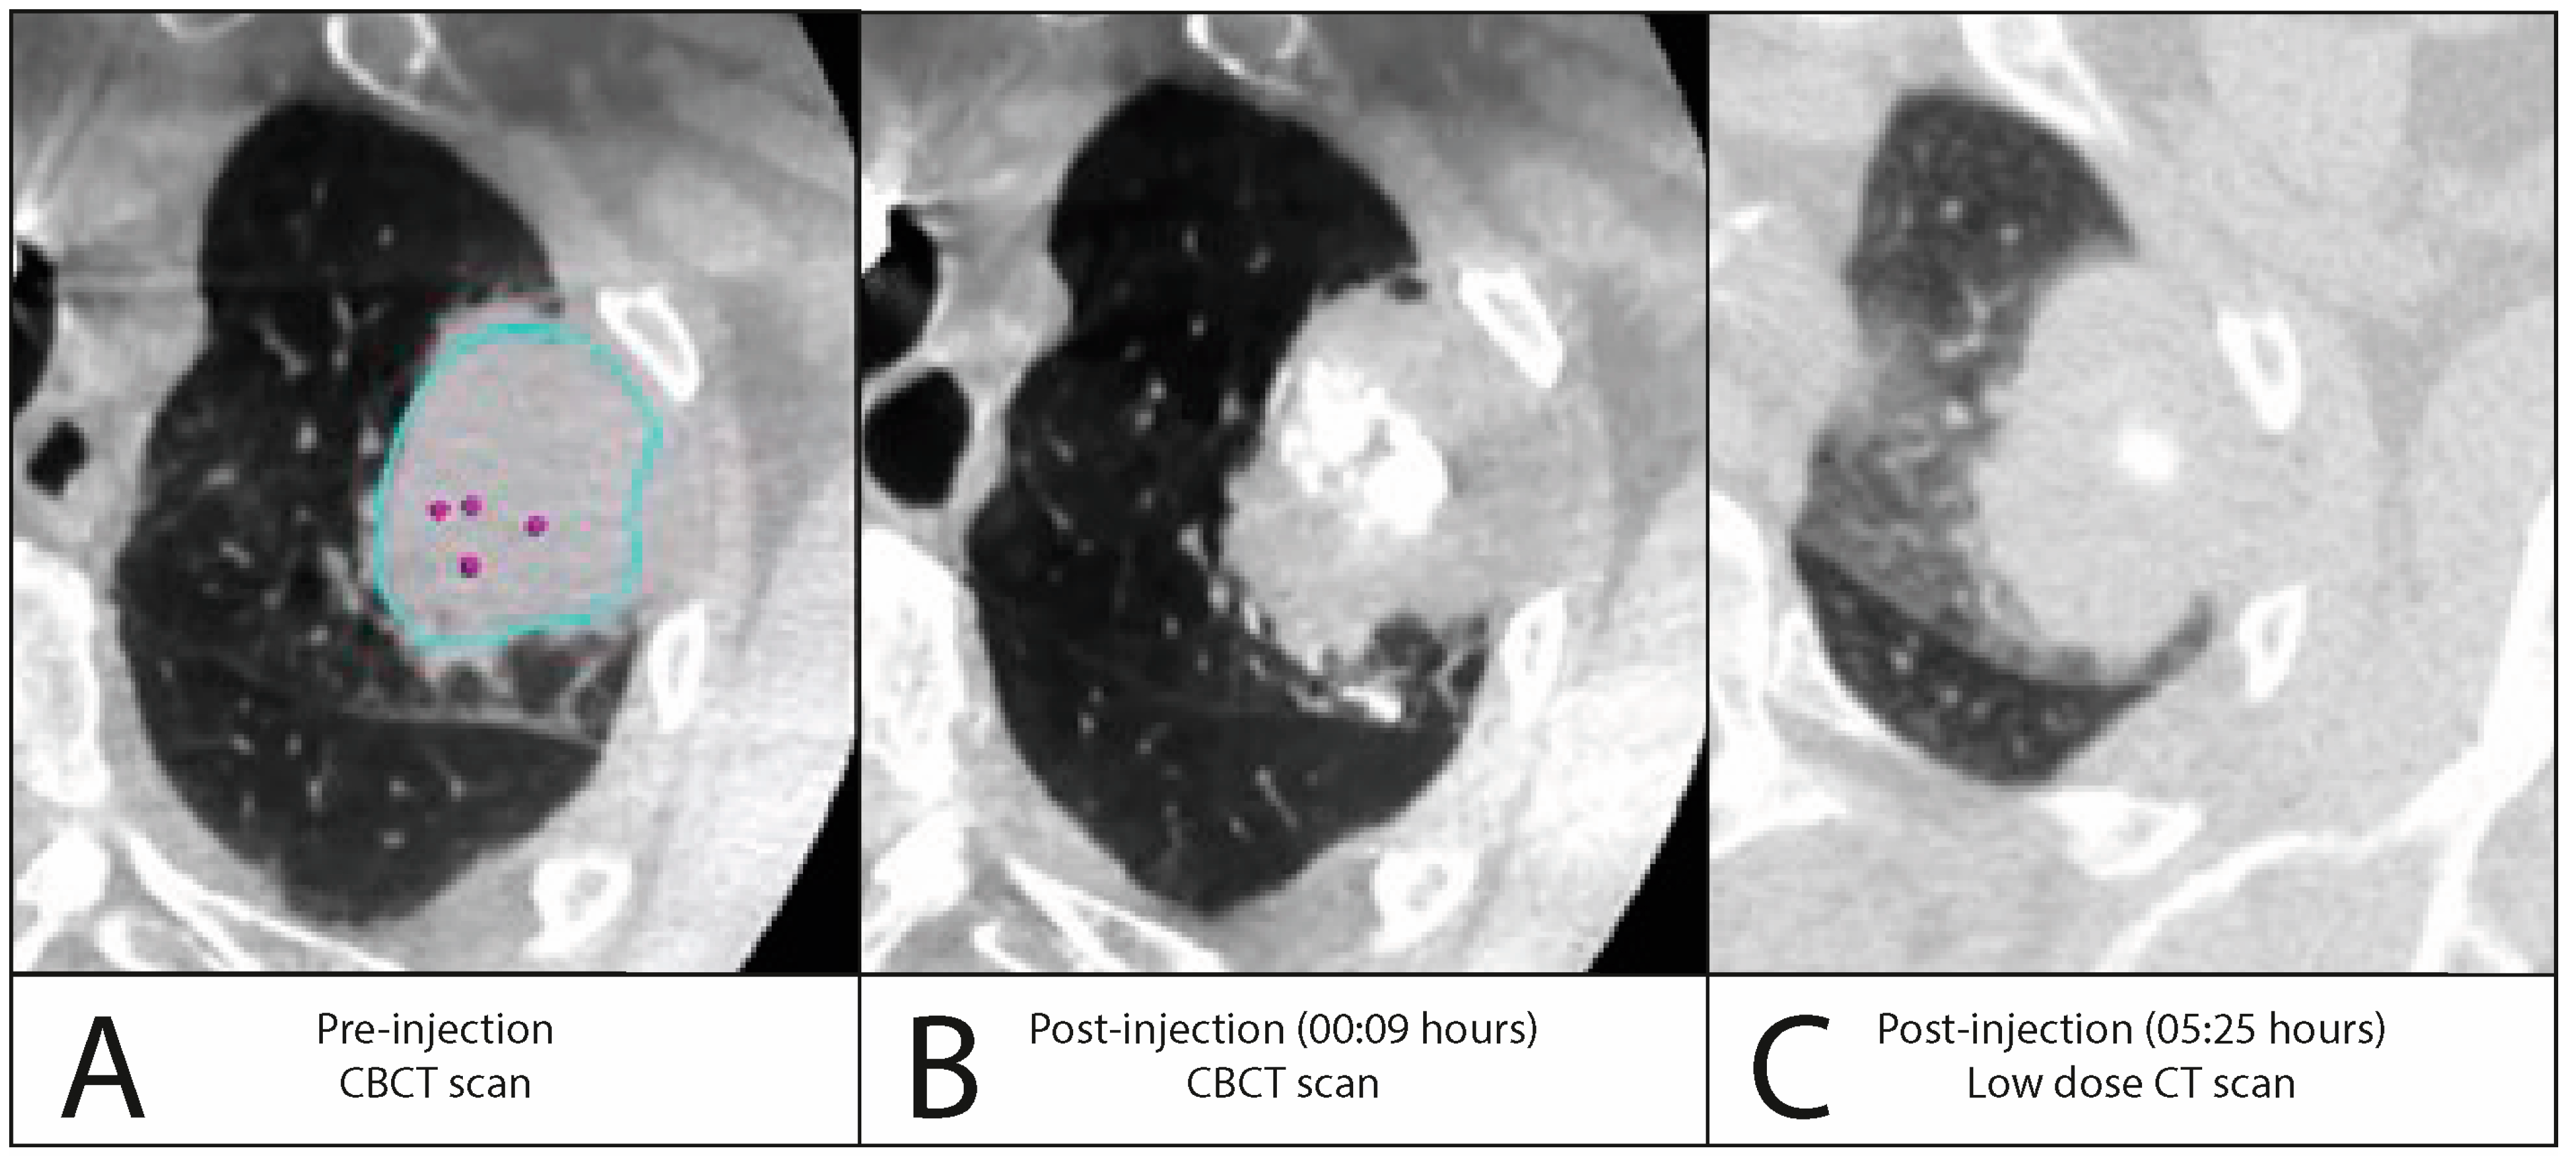

3.2.2. Iodinated Contrast Injection

| Iomeron 300 | Number of patients with injection(s), n (%) | 15 (48.4%) | |

| Injection volume, mL, median (±IQR) | 0.30 (±0.20) | ||

| Injection visible on fluoroscopy, n (%) | 15 (100%) | ||

| Leakage visible on fluoroscopy, n (%) | 4 (26.7%) | ||